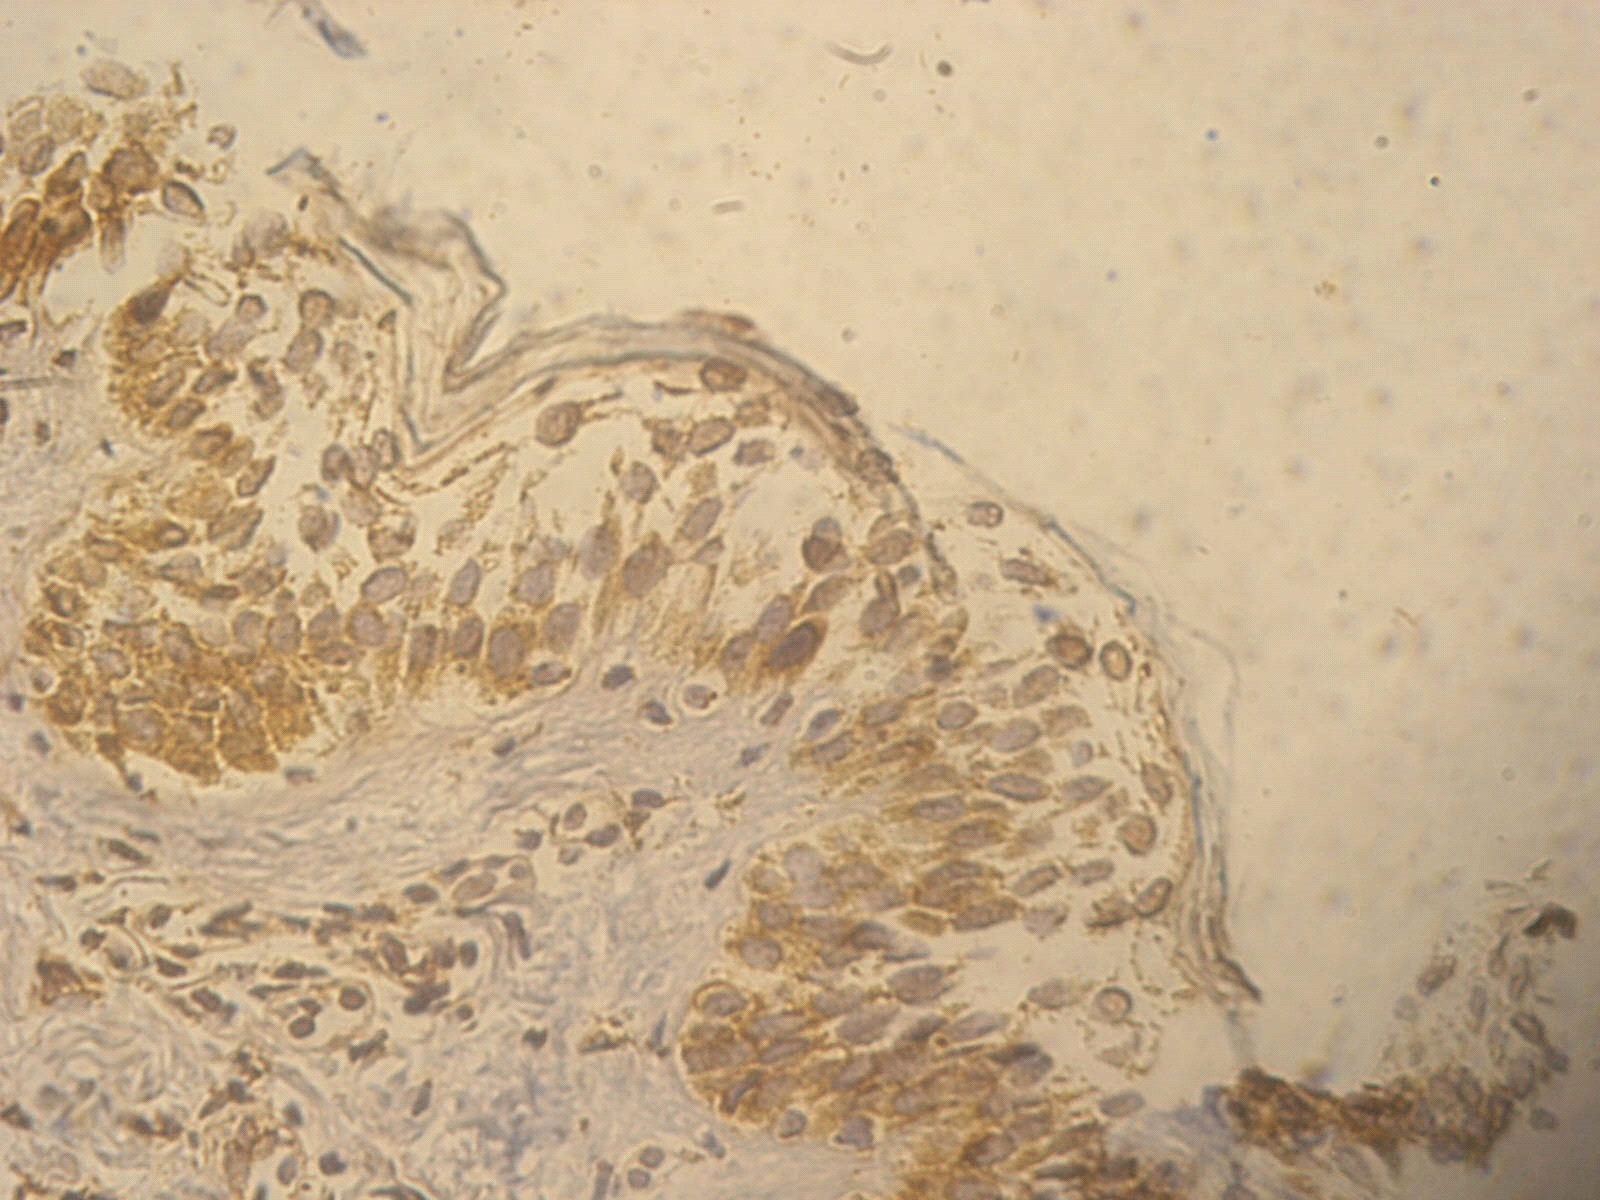

Figure 5. +2 ssDNA positive apoptotic epidermal cells in a lesional segmental Vitiligo case (immunohistochemical stain, x400).

Among the lesional biobsies there were 3 patients (15%) with +2 and 17 patients (85%) with +3 positivity staining for  PGP9.5,  while in the non lesional ones there were 11 patients (55%) with +1 and 9 patients (45%) with +2 positivity staining for PGP9.5. Lesional biopsies also showed that there were 12 patients (60%) with +2 and 8 patients (40%) with +3 positivity staining for ssDNA and the  non lesional ones showed 18 patients (90%) with +1 and 2 patients (10%) +2 staining for ssDNA (Table 1 and Figures 1-6).